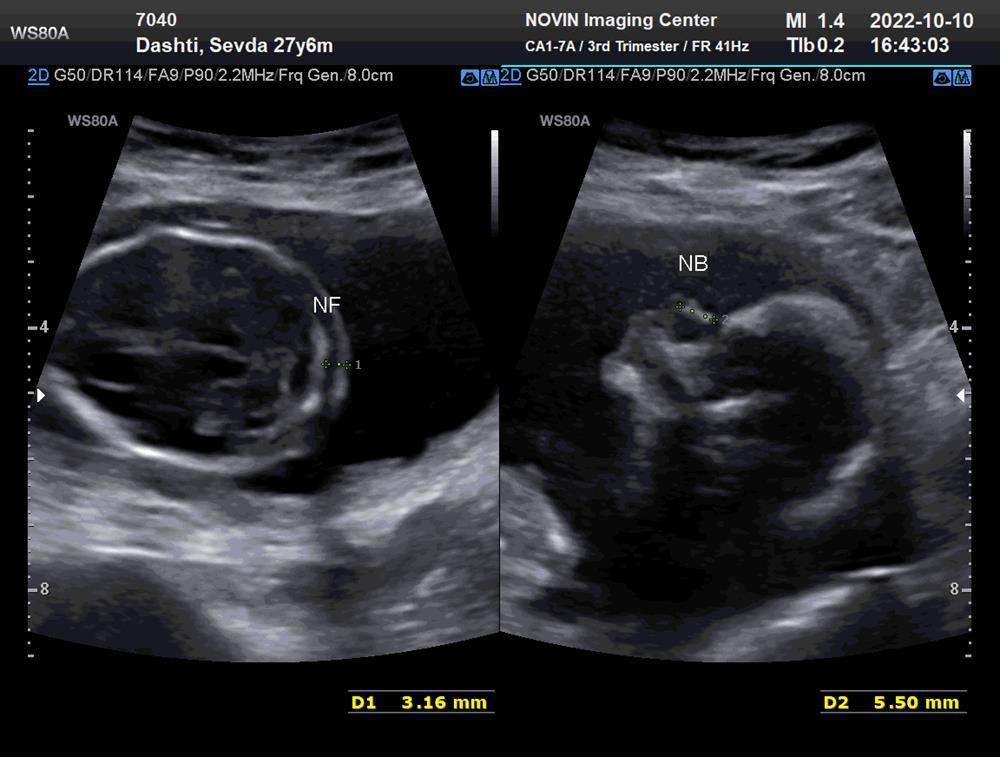

بنظرتون جنسيت چيه ؟؟

آره عزیزم نزدیک دوسالشه،،بعد وقتی جنین حالت نیم خیز داره چونش نزدیک قفسه سینش معمولا میگن پسره

۱۶هفته رفتم گفت دختره ولی باشک گفت

منم حس میکنم دختره ۱۶ هفته هم شکی توش نیست انشالله سالم وسلامت باشه